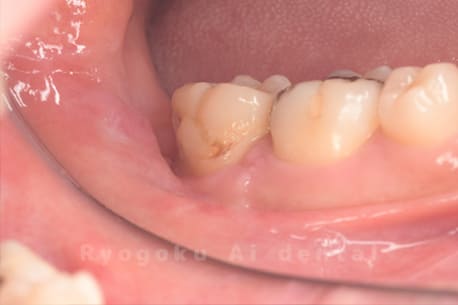

Case21

-

- 原因

- 重度カリエス

- 治療内容

- クラウンレングスニング

- 治療費用

- 44,000円

他院で抜歯と宣告され、当医院を受診された患者様です。クラウンレングスニングを行い、保存を行いました。経過良好です。

<リスク・副作用>

手術後は痛み、腫れ、痺れ、青あざなどの副作用が生じます。痛みは痛み止めを処方しますが、腫れ、青あざは1週間程度生じる場合があります。また、部位によっては神経の走行が複雑で、痺れが残り、長期的にお薬を処方する場合があります。